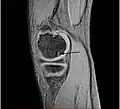

Magnetic resonance imaging (MRI) is useful for staging OCD lesions, evaluating the integrity of the joint surface, and distinguishing normal variants of bone formation from OCD by showing bone and cartilage edema in the area of the irregularity. MRI provides information regarding features of the articular cartilage and bone under the cartilage, including edema, fractures, fluid interfaces, articular surface integrity, and fragment displacement.[37][38] A low T1 and high T2 signal at the fragment interface is seen in active lesions. This indicates an unstable lesion or recent microfractures.[30] While MRI and arthroscopy have a close correlation, X-ray films tend to be less inductive of similar MRI results.[38]

Sagittal MRI: Linear low T1 signal at the articular surfaces of the lateral aspects of the medial condyle of the femur confirms the presence of OCD.